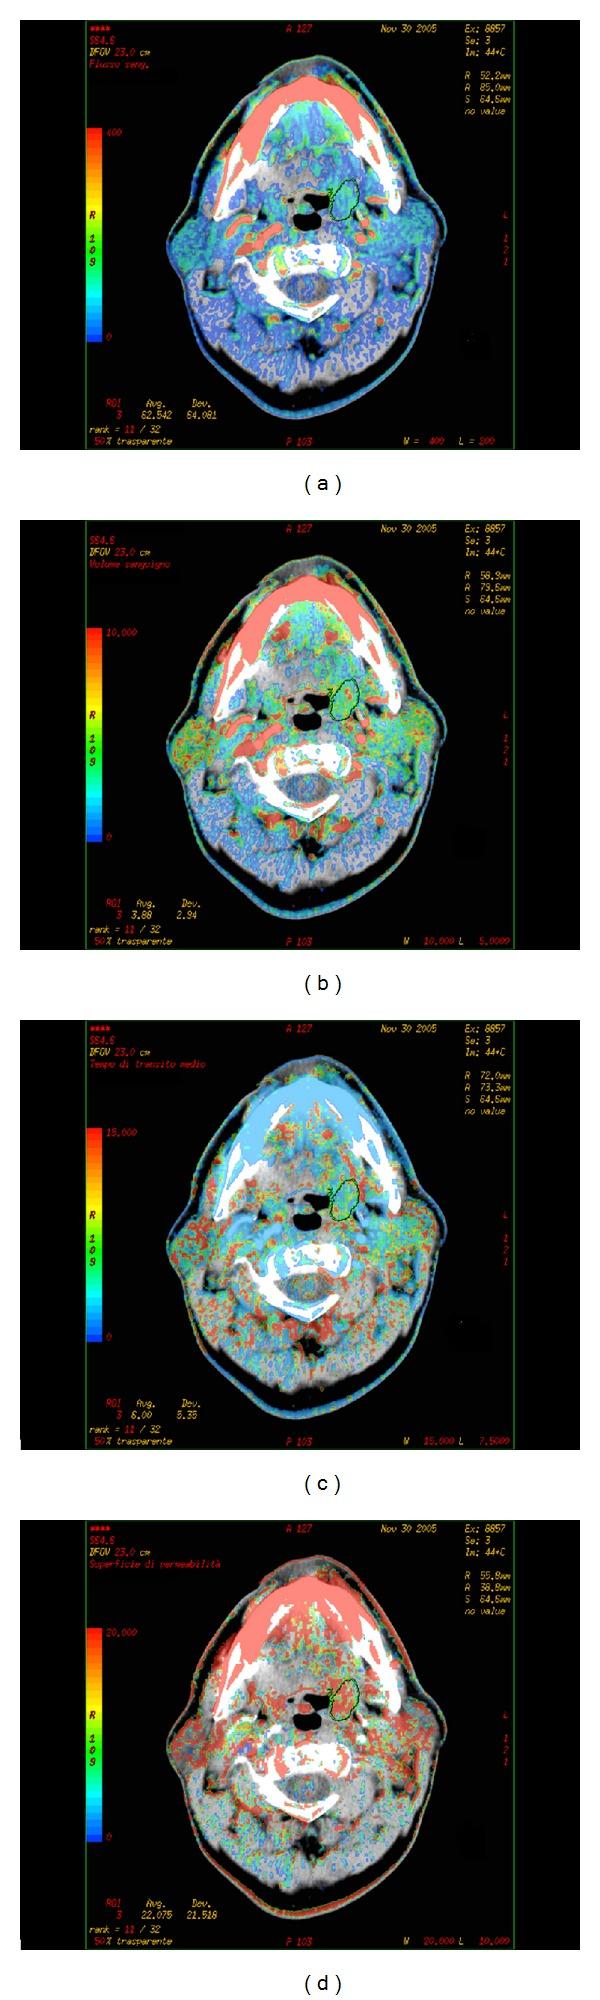

This review aims to summarize the technique and clinical applications of CT perfusion (CTp) of head and neck cancer. The most common pathologic type (90%) of head and neck cancer is squamous cell carcinoma (HNSCC): its diagnostic workup relies on CT and MRI, as they provide an accurate staging for the disease by determining tumour volume, assessing its extension, and detecting of lymph node metastases. Compared with conventional CT and MRI, CTp allows for obtaining measures of tumour vascular physiology and functional behaviour, and it has been demonstrated to be a feasible and useful tool in predicting local outcomes in patients undergoing radiation therapy and chemotherapy and may help monitor both treatments.

本综述旨在总结头颈部癌CT灌注(CTp)技术及其临床应用。头颈部癌最常见的病理类型(90%)是鳞状细胞癌(HNSCC):其诊断检查依赖于CT和MRI,因为它们通过确定肿瘤体积、评估其范围以及检测淋巴结转移为疾病提供准确分期。与传统CT和MRI相比,CTp能够获取肿瘤血管生理学和功能行为的相关测量值,并且已被证明是预测接受放疗和化疗患者局部预后的一种可行且有用的工具,还可能有助于监测这两种治疗。